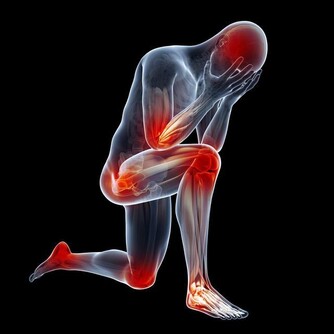

在生活中,大多數人都有過抽筋的經歷。肌肉痙攣,俗稱抽筋,是一種肌肉自發的強直性收縮,發生在小腿和腳趾的肌肉痙攣最常見,發作時疼痛難忍,可持續幾秒到數十秒之久。尤其是半夜抽筋,往往能把人痛醒。有些人覺得腿抽筋了,一定是缺鈣了。其實,有很多原因都會導致“抽筋”,具體情況需要具體分析,我們才能對症下藥。

過度疲勞長時間徒步、跑步、爬山、提重物或者常年整天穿高跟鞋的女性,運動時肌肉緊張會導致局部血管一過性狹窄,肌肉血供不佳,引起肌肉痙攣。此外,長時間運動、人體大量出汗時,且沒有及時補充水分和鹽,會伴有電解質(鉀、鈉等)大量的丟失,導致電解質紊亂。這時,肌肉興奮性異常也容易發生痙攣。

寒冷當溫度下降時,我們四肢肌肉特別是小腿肌肉的血管為了減少熱量散失會收縮,於是,流經此處的血流速度變緩,氧氣供應不足,代謝廢物堆集過多,容易引起小腿肌肉痙攣。比如游泳之前沒有充分熱身就立即下到低溫度的泳池裡、冬天手腳保暖不充分、夏天吹空調冷氣或電風扇吹腳、晚上睡覺沒蓋好被子等情況下都可能會引發抽筋。所以經常出現抽筋的人要注意手腳的保暖。

局部長時間壓迫當局部肌肉長時間處於某一姿勢時,受壓過久,易導致下肢血液循環受阻,代謝能力變差,肌肉中的乳酸代謝物堆積,也會發生肌肉痙攣。這種情況尤其常見於肥胖、孕婦、老年人等人群。

下肢動脈硬化閉塞症小腿抽筋頻繁,還要警惕血管性疾病可能,尤其是老年人。下肢血管硬化時,管腔會變窄,導致局部供血不足、血液循環不暢,組織缺氧及代謝產物蓄積,會使得肢體末端因為缺血出現抽筋、疼痛等不適。如果治療不及時,血管狹窄會逐漸加重,甚至引起外周器官營養缺乏,嚴重時發生壞疽等不良後果。